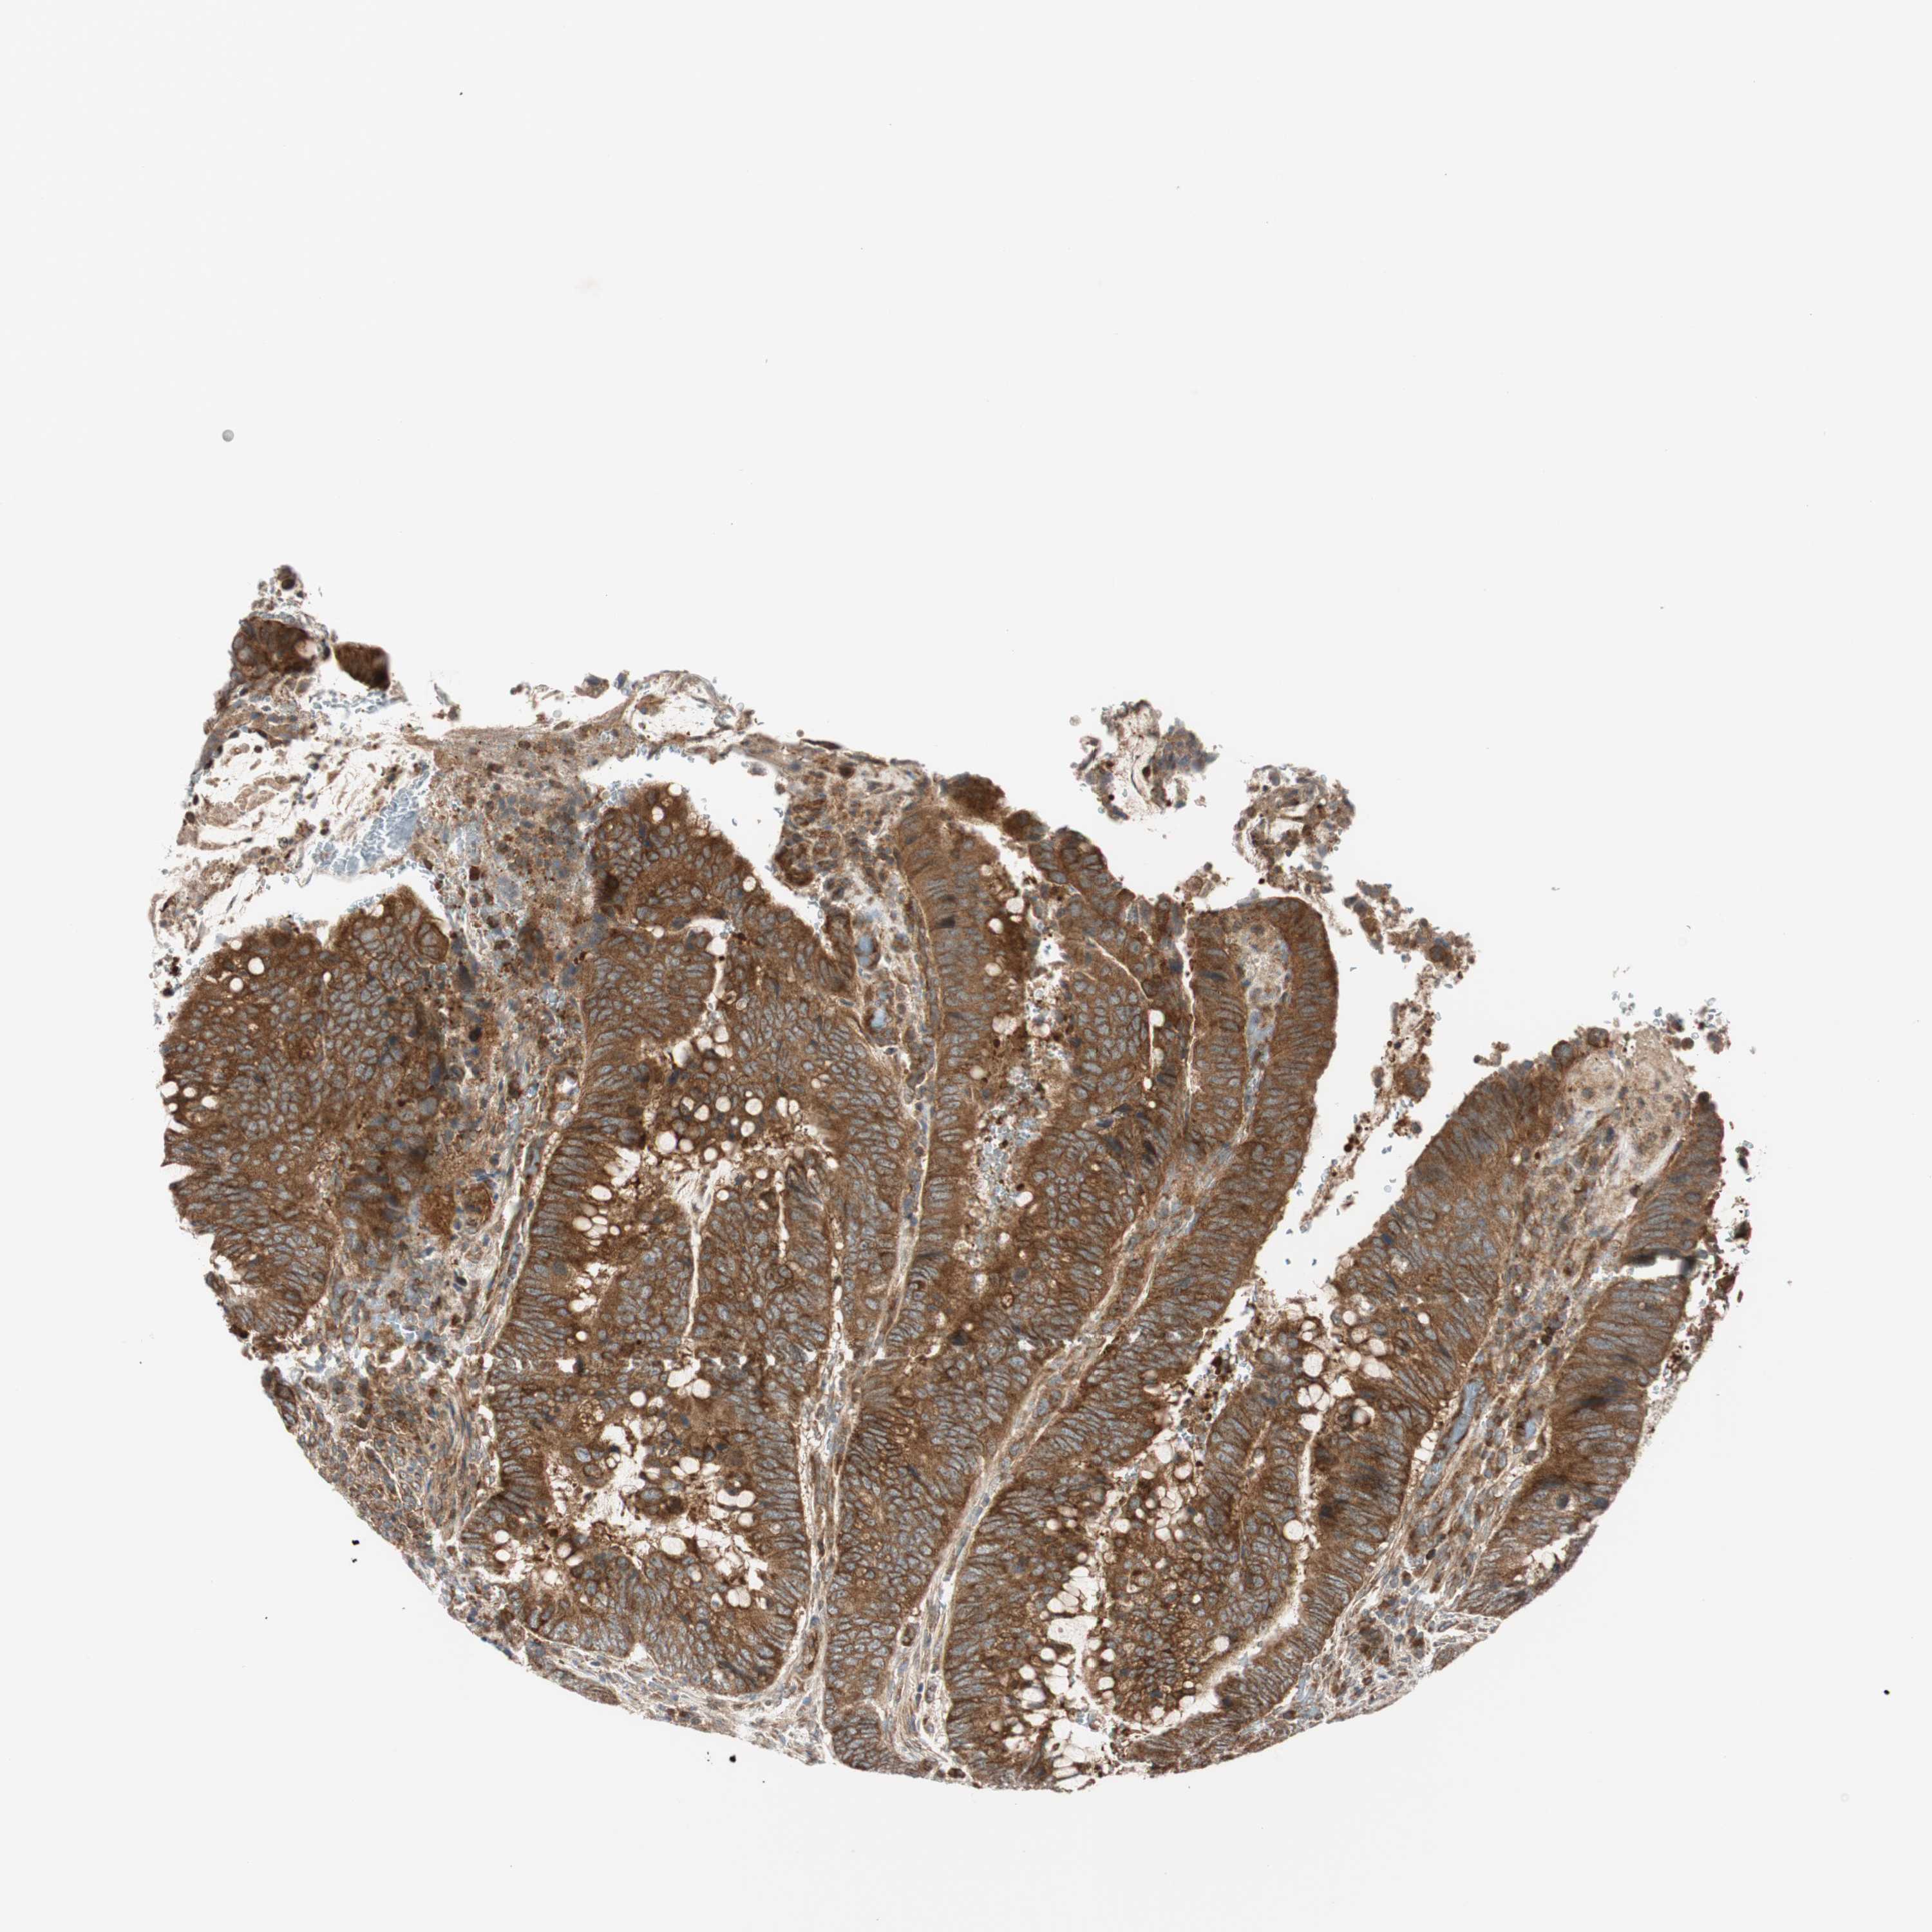

CANCER COLORECTAL CANCER Show tissue menu

Colorectal cancer

Human cancer

Colon adenocarcinoma